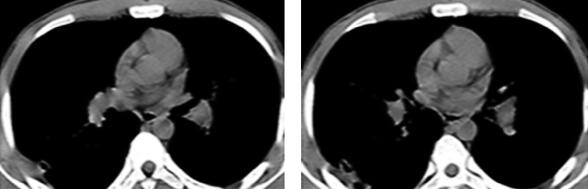

停用华法林观察1周,咯血和气短症状逐渐缓解,2013年4月14日复查胸部CT与2013年4月5日相比较,新发的磨玻璃影全部吸收,进一步证实为肺泡积血导致;而左肺下叶沿支气管走行斑片影、粟粒影与2013年4月5日比较明显吸收,原右下叶空洞较前进一步缩小(图7)。结合患者临床表现和影像学特征,考虑咯血原因为华法林药物副作用和(或)肺栓塞导致肺梗死所致,故改为低分子肝素皮下注射抗凝治疗。后咯血逐渐减少,出院后继续规律低分子肝素治疗。2013年5月22日患者门诊随访,无咯血,无气短,无胸痛,无发热,复查胸部CT示右下肺空洞基本吸收,遗留两个薄壁的小空腔及少许条索影(图8)。考虑患者为青年学生,久坐习惯可去除,规范低分子肝素皮下注射抗凝治疗总疗程3个月后停止抗凝。2013年10月16日复查CTPA提示未见肺动脉充盈缺损。

图7

图8